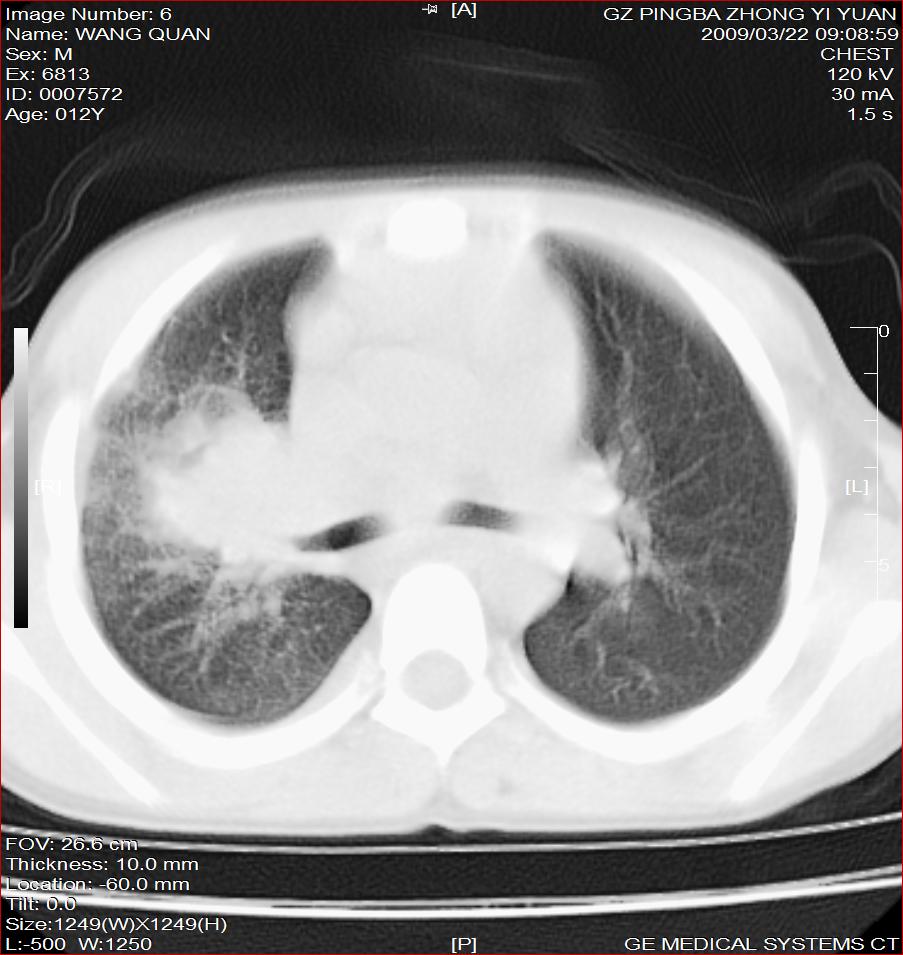

以下是引用随光逐影在2009-3-23 8:12:00的发言:[br]1)右肺门及纵隔淋巴结结核。2)两肺急性血行播散型肺结核可能。3)右侧支气管内膜结核?建议必要时行纤支镜检查。4)右侧少量胸腔积液。